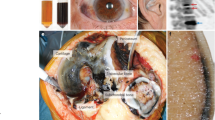

Moreover, amyloid was detected also in heart (Millucci et al 2014a, c), prostatic stones, periumbelical abdominal (Millucci et al 2012), and articular fat and labial salivary gland (Millucci et al 2014d) of tissues from ochronotic patients (Fig. 2), thus suggesting the systemic nature of AKU-related amyloidosis and the case of a secondary amyloidosis. In fact, SAA deposition was revealed in all AKU amyloid specimens (Millucci et al 2012, 2014a, b, c, d), clearly indicating that AA amyloidosis is related to ochronosis. Immunofluorescence also allowed highlighting the co-localization of amyloid with the melanin-like ochronotic pigment that has intrinsic fluorescence properties (Millucci et al 2012, 2014a, c, d; Spencer et al 2004; Spreafico et al 2013), and such superimposition was particularly remarkable in correspondence of synovial ochronotic shards and in AKU aortic valve (Millucci et al 2012, 2014a, c). Localized amyloid was noted in ochronotic cartilage in all cases (Millucci et al 2012, 2014b; Spencer et al 2004), and calcium pyrophosphate crystals deposition was also seen in knee and elbow joints (Spencer et al 2004). Immunohistochemistry confirmed the presence of SAP component in all AKU tested specimens, while no positivity was observed for the presence of immunoglobulin light chains, pre-albumin, beta-2 microglobulin, α-synuclein, and Pmel17 (Millucci et al 2012; Spencer et al 2004). Transmission electron microscopy (TEM) observations indicated that the amyloid fibrils detected in AKU tissues ranged 6-13 nm in diameter and were always in close proximity of ochronotic pigmented areas (Millucci et al 2012, 2014a, c; Millucci et al 2014d) (Fig. 2). Apart from visible signs of cell death and autophagy, dense layers of amyloid and scattered amyloid aggregates and fibrils among collagen fibres were always evident. These latter appeared usually strongly loaded by drop-like pigment elements as also previously reported (Taylor et al 2010).

TEM observation of amyloid in AKU tissues. Articular AKU cartilage showed the presence of aggregates of amyloid fibrils between recognizable broken collagen fibrils, finally sprinkled with pigment drop-like granules (bar 2.5 μm). AKU aortic valve revealed the presence of intracellular and extracellular deposits of ochronotic pigment. A massive infiltration of fine amyloid fibrils in proximity of a large pigment patch is shown (bar 100 nm). AKU salivary gland is the tissue where amyloid deposits were observed more abundantly. Ultrastructural observation showed a region of the interstitial glandular stroma that contained fine amyloid fibrils, interspersed with bundles of collagen fibrils. Pigment deposits were present on broken collagen fibres scattered between amyloid fibrils (bar 2.5 μm). AKU knee fat showed the presence of numerous and pervading long, straight and parallel bundles of amyloid fibrils (bar 5 μm)

HGA, if injected into joints produces disabling damage, ochronosis, necrosis and inflammatory reactions (Martin and Batkoff 1987). Indeed, an inflammatory status can be observed in AKU tissues (Selvi et al 2000; Taylor et al 2010), where macrophages may surround the pigmented areas (Taylor et al 2010), while HGA-treated chondrocytes and synoviocytes show phagocytic features (Castillo and Kourí 2004). Local inflammation signs have been previously reported in AKU (Selvi et al 2000). Lymphocyte aggregates and infiltrating macrophages were found in the synovial (Fig. 3) and aortic valve tissues (Millucci et al 2014a, c), especially in the proximity of ochronotic shards. In AKU aortic valves large deposits of ochronotic pigment were found in the vicinity of areas of valvular calcification, tissue fibres adjacent to calcium deposits interconnecting bundles of collagen were demonstrated and EDS spectra of pigmented areas of AKU aortic valve proved the presence of indicate hydroxyapatite concretions (Millucci et al 2014a, c). Such a valvular calcification, typical of stenosis, is always in strong correlation with an inflammatory local condition (Dweck et al 2012).

Haematoxylin and eosin histology of AKU synovia indicates local inflammation. Representative haematoxylin and eosin micrographs of synovium biopsies from an AKU total knee (left) and shoulder (right) arthroplasty (both magnification 40×). Synovial membrane showed hyperplasia of the lining layer with a region of predominantly lymphocytic inflammation in the sublining layer with plasma cells and macrophages. Ochronotic cartilage shards embedded in severely degraded synovium were evident. Dense cellularity with inflammatory cells, containing many or large lymphoid aggregates were also present. Lymphocytes, macrophages and even clumps of plasma cells infiltrating the sublining region, mainly in correspondence of large ochronotic shards were visible. The synovial intimal lining, here not appreciable due to the extremely decayed conditions of the tissue, was ever hyperplastic with an increased number of macrophages and fibroblasts